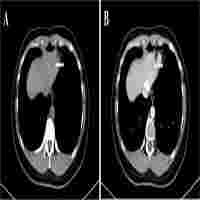

| Abstract | With microtrauma becoming a consensus, in order to improve surgical treatment capability, the clinical application of laparoscopic multiorgan resection is becoming more and more complicated and diversified. Recently, we successfully presented a case of transvaginal specimen extraction surgery that included laparoscopic anatomical left hemihepatectomy combined with laparoscopic total hysterectomy and bilateral adnexectomy and the pelvic and para-aortic lymphadenectomy. The patient, a 75-year-old woman, was hospitalized with abnormal vaginal discharge and bleeding. The pathologic diagnosis of uterine curettage was endometrioid adenocarcinoma. After completing examinations such as color Doppler ultrasound, CEUS, MRCP and thoracoabdominal enhanced spiral CT, preoperative diagnosis was considered as endometrial cancer and a space-occupying lesion in the liver (primary or secondary site?). No lymphatic or distant metastasis had been found. We also excluded Lynch syndrome by digestive endoscopy and gene sequencing. After a multidisciplinary consultation, the patient underwent surgery under general anesthesia on 24 September 2021. The operation was completed uneventfully in 6 hours, then the patient was transferred to the ICU for follow-up monitoring. The patient began to eat and was able to leave bed on the 4th postoperative day. According to immunohistochemistry, the patient's postoperative diagnosis was intrahepatic cholangiocarcinoma (ICC) and endometrial cancer. Compared with open surgery, laparoscopic multiorgan resection with natural orifice specimen extraction surgery (NOSES) has many advantages such as fewer traumas, shorter recovery time, and better postoperative quality of life. However, combined large-scale laparoscopic surgeries of different organs can be challenging for surgeons and anesthesiologists. No similar cases have been searched. |